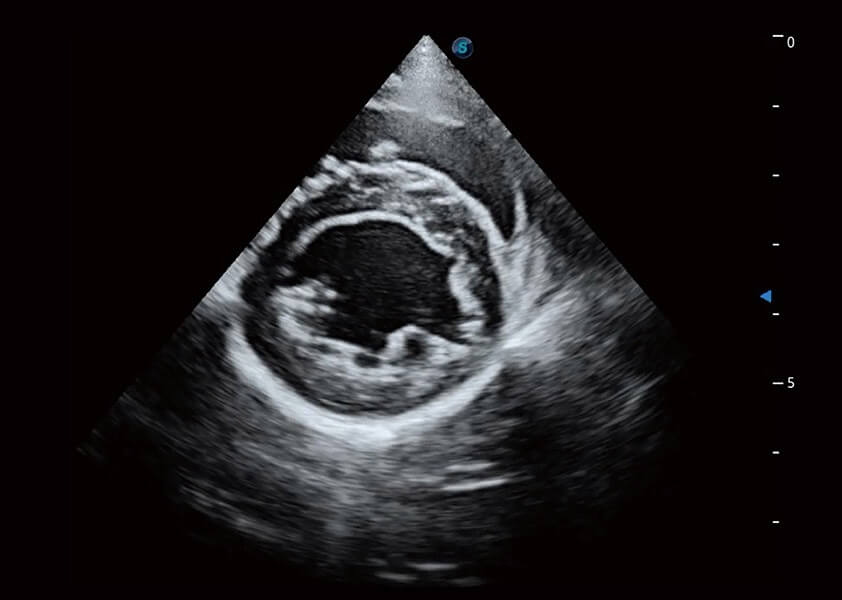

ProPet 60 作为一款高端台式动物超声设备,为动物医生的日常诊断提供了一系列贴合动物临床需求、解决临床实际问题的高级成像功能。凭借全系列高清探头,满足医生对腹部、心脏、生殖、浅表、肌骨等成像的所有需求,切实帮助您提升检查效率,提高诊断信心。

动物是人类最亲密的朋友和最值得信赖的伙伴。哈哈体育官网也一直致力于探索动物专用的超声影像解决方案。 全新推出的ProPet系列,是哈哈体育官网在动物超声影像智能化、专业化、精准化的一次跨越式革新。动物不能用言语来表述自己的不适,通过超声影像,ProPet系列搭建了动物医生与不同物种沟通的“桥梁”,为动物医生注入了“治愈之力”。